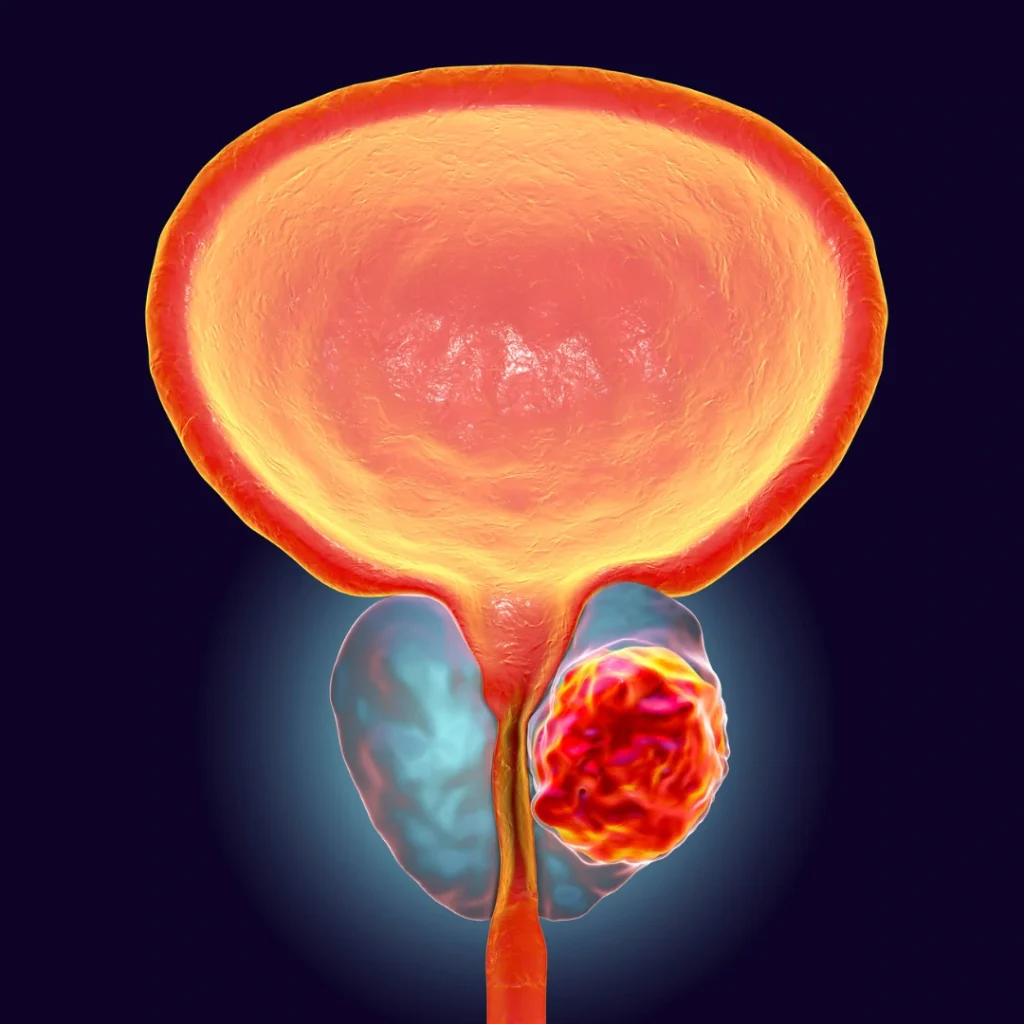

O câncer de próstata (adenocarcinoma da próstata) é a neoplasia maligna mais comum em homens no Brasil, excluindo os tumores de pele. Fatores de risco incluem idade avançada e histórico familiar. É importante saber que não há medidas dietéticas preventivas específicas comprovadas.

Em fases iniciais, o câncer de próstata raramente apresenta sintomas. Sintomas urinários, como jato fraco, são geralmente causados por crescimento benigno da próstata (hiperplasia prostática benigna – HPB). Quando há sintomas relacionados ao câncer de próstata, como retenção urinária, disfunção erétil, dilatação do rim ou dor óssea, o câncer já é localmente avançado ou metastático. A suspeita de câncer de próstata surge com exames de rotina, como o PSA (sangue) e o toque retal. A ressonância magnética pode guiar a necessidade de biópsia, que é o único exame que confirma o diagnóstico.

A maioria dos casos é detectada em estágio inicial e é curável. O câncer pode estar localizado ou ter se espalhado (doença metastática). O escore de Gleason e os graus ISUP classificam a agressividade do tumor. Exames como Cintilografia Óssea, Tomografia e, principalmente, PET-CT com PSMA, avaliam a extensão da doença.

Uma característica notável do câncer de próstata , mesmo em sua fase inicial e restrito à glândula, é sua natureza multifocal. Isso significa que múltiplos focos tumorais podem coexistir dentro da mesma próstata, o que representa um desafio significativo para a eficácia de terapias focais, como o HIFU (Ultrassom Focalizado de Alta Intensidade), ou ressecções parciais. Por essa razão, os tratamentos locais mais estabelecidos e eficientes para curar o câncer de próstata localizado geralmente envolvem a abordagem de toda a glândula. Para os casos de câncer de próstata avançado ou metastático, são necessárias combinações de tratamentos sistêmicos, os quais se mostram muito eficazes no controle da doença e na melhoria da qualidade de vida do paciente.